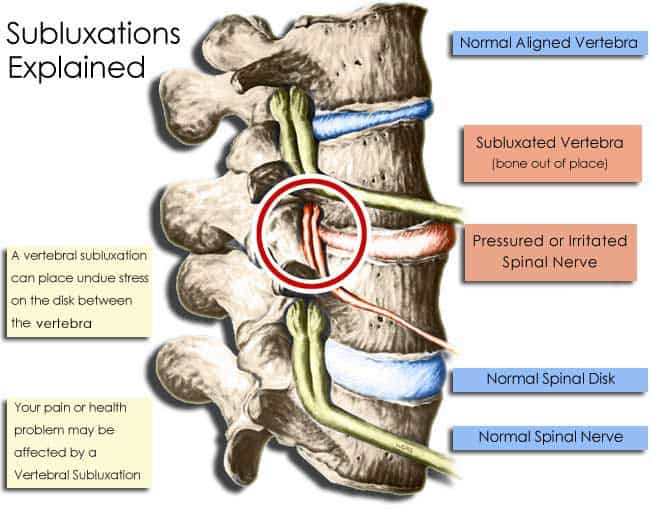

In simplest terms, a subluxation (a.k.a. Vertebral Subluxation) is when one or more of the bones of your spine (vertebrae) move out of position and create pressure on, or irritate spinal nerves. Spinal nerves are the nerves that come out from between each of the bones in your spine. This pressure or irritation on the nerves then causes those nerves to malfunction and interfere with the signals traveling over those nerves.

The osseous (bone) component is where the vertebrae are either out of position, not moving properly, or are undergoing physical changes such as degeneration. This component is sometimes known as kinesiopathology.

The Nerve Component is the malfunctioning of the nerve. Research has shown that only a small amount of pressure on spinal nerves can have a profound impact on the function of the nerves. This component is scientifically known as neuropathology.